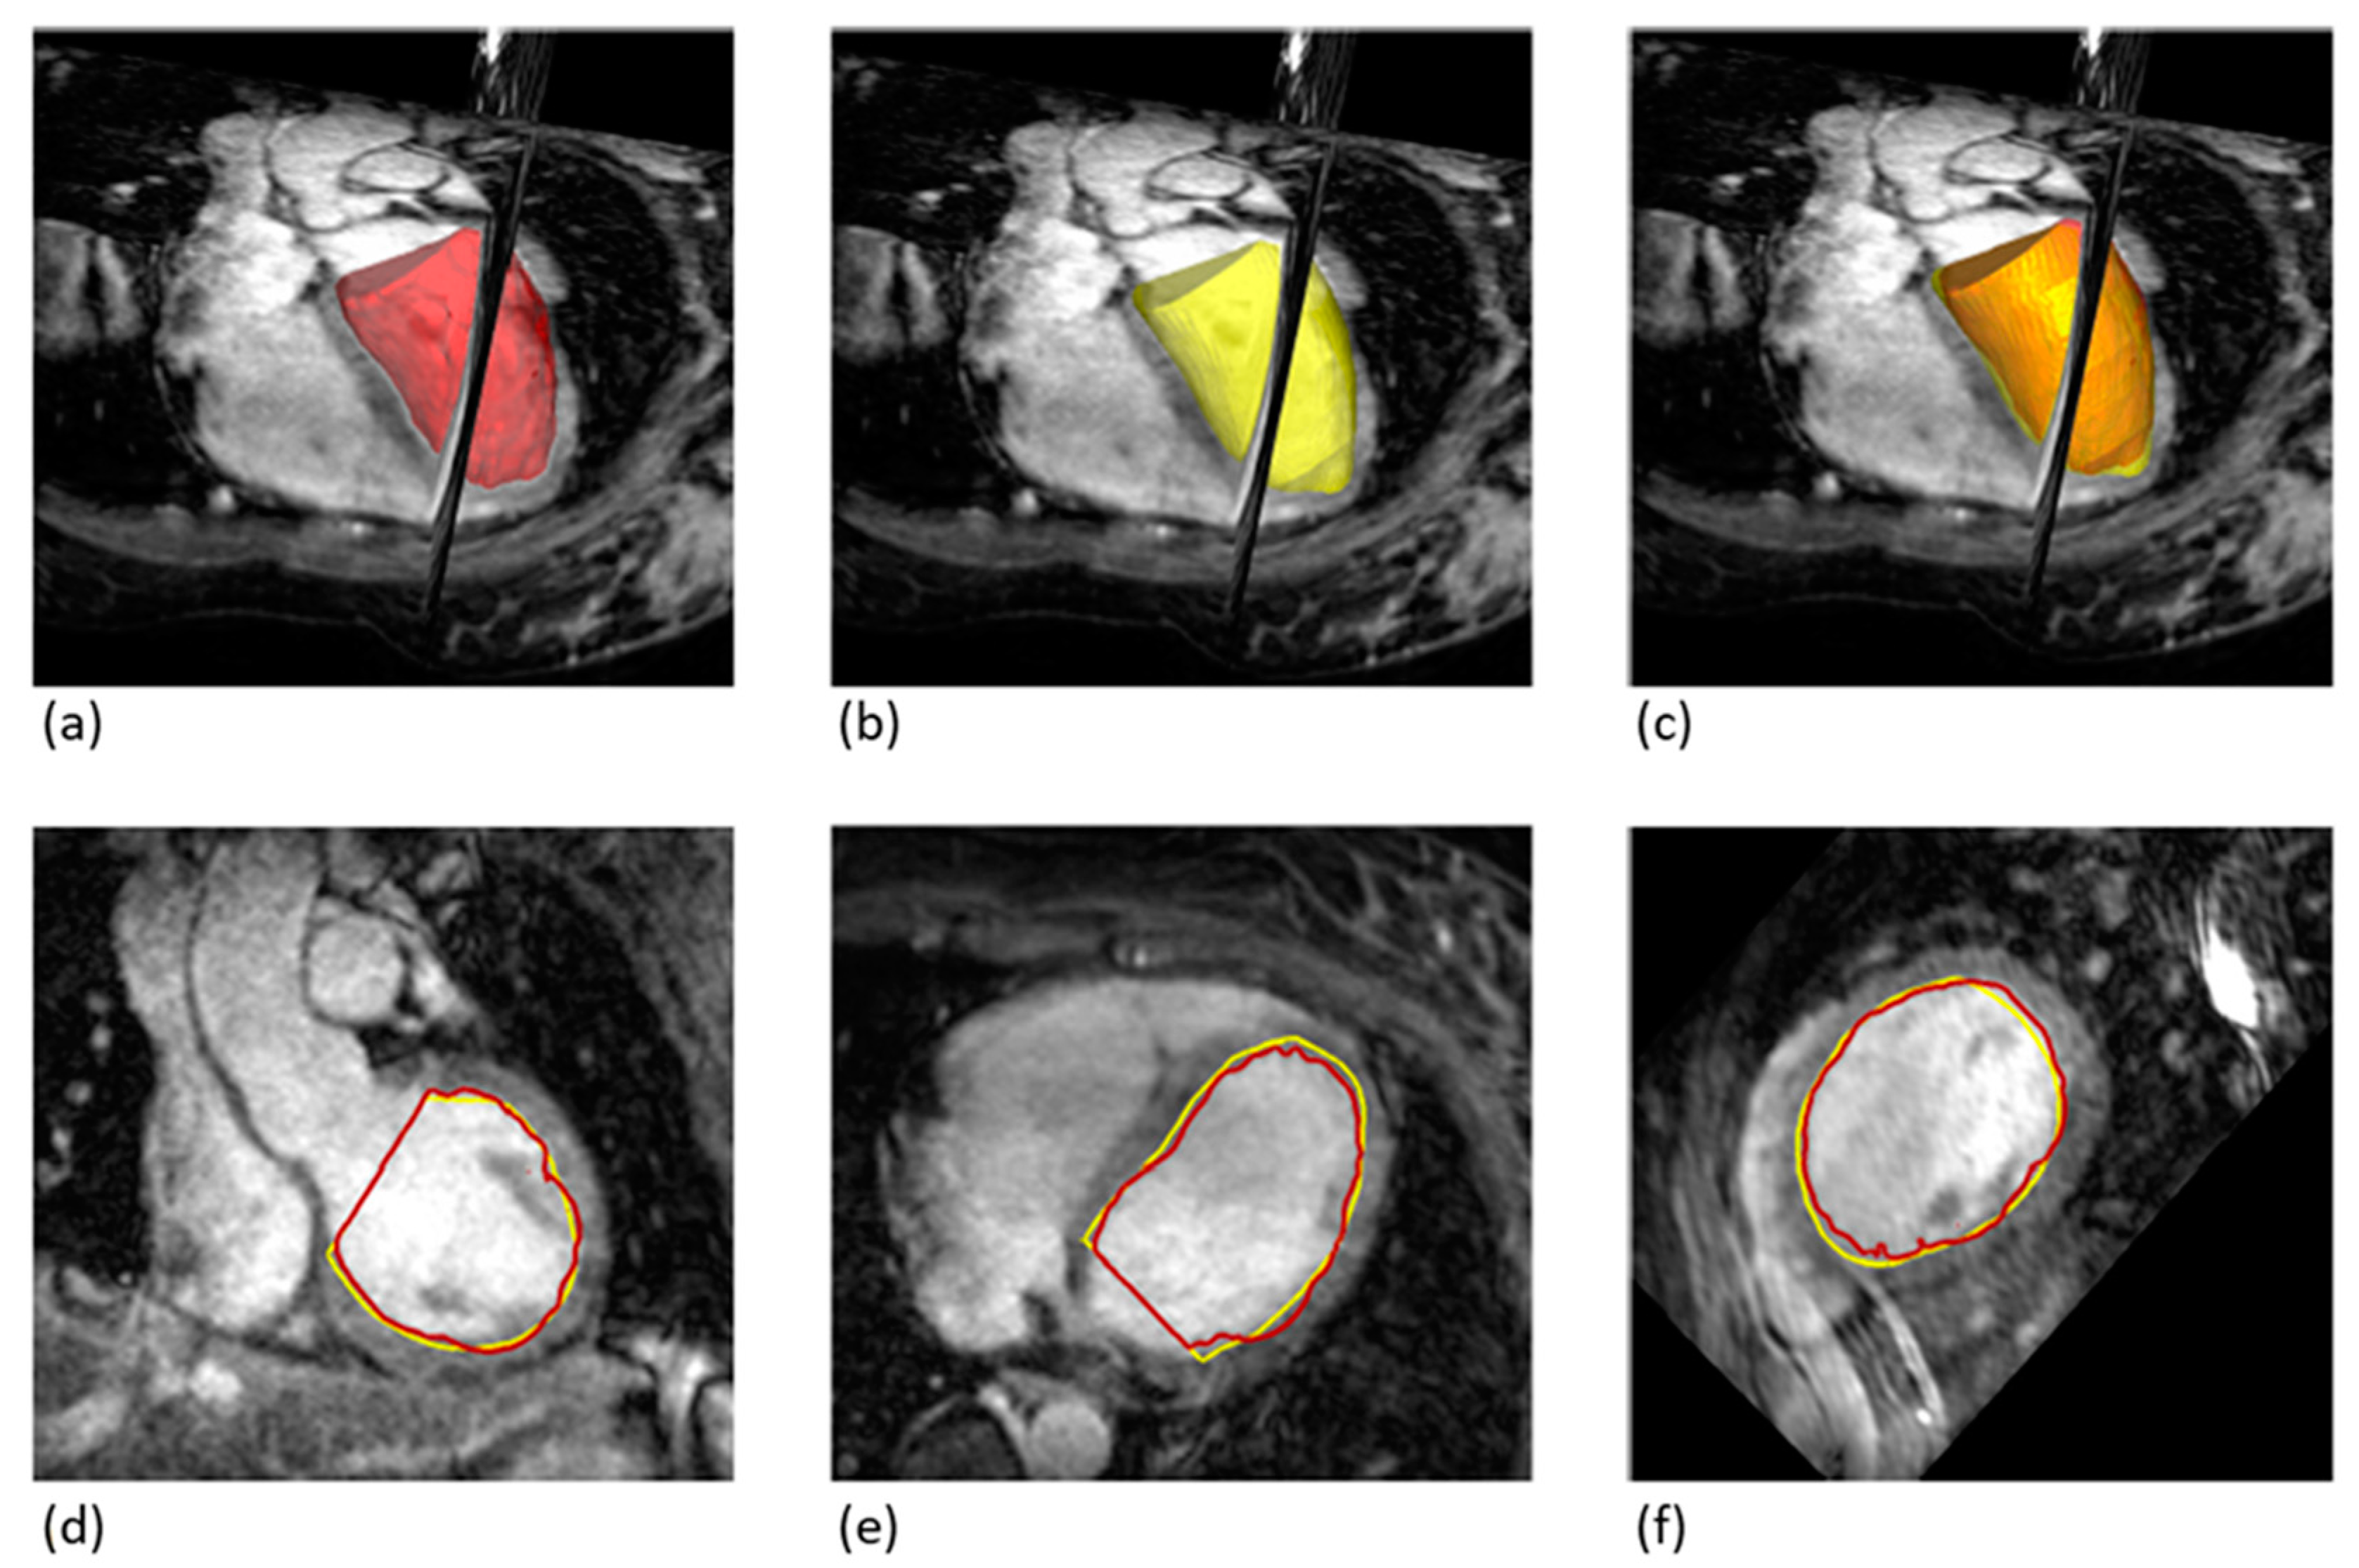

Figure 4. Comparison of Overlapping Volumes between 2D-cine and 3D-wh Techniques. (a) 3D Volume Reconstruction using 3D-wh (red), showing a reconstructed cylinder for direct comparison (3D-wh-cylinder). (b) 3D Volume Reconstruction using 2D-cine (yellow). (c) Merge of A and B, illustrating the degree of overlap between the 3D-wh and 2D-cine volumes. (df). Endocardial Overlapping in Different Slice Planes.

3.3. Degree of Overlap between 3D Volumes from Cine and Whole-Heart Sequences

Both the 2D-cine and whole-heart procedures involve creating a volumetric representation of the endocardium at end-systole and end-diastole, which is then used to measure the three-dimensional degree of overlap. The comparative analyses are conducted between the 3D-wh-cylinder and the 2D-cine volumes (see Section 2).

Figure 4 illustrates the deviations of the contours between the 2D-cine and 3D-wh volumes. It clearly demonstrates a strong overlap between the two volumes, a finding further supported by the congruence analysis (Table 2). The Dice coefficient reveals an overlap of 90%, with a mean deviation of less than 2 mm. Notably, there is no significant difference in the overlap between diastole and systole.